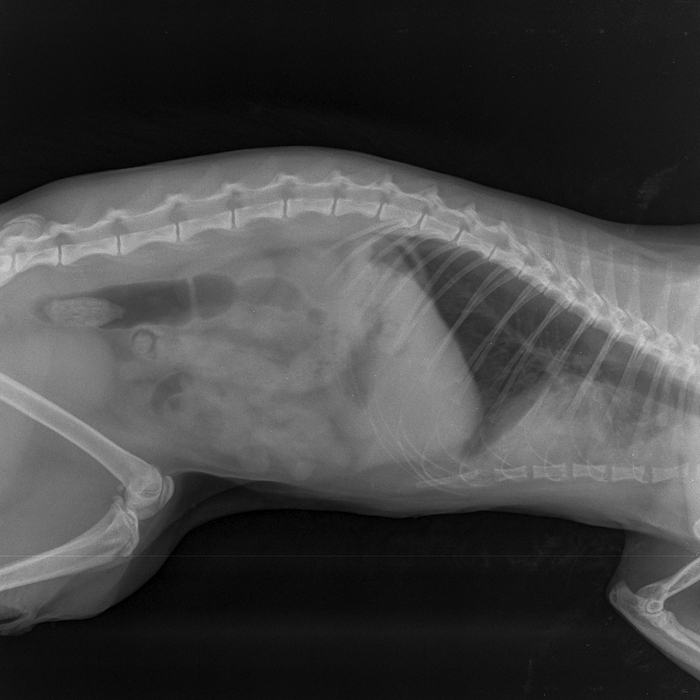

2 августа эта красота решила отметить праздник. Отодрала сетку с балконного окна и сиганула с 5 этажа без парашюта (скорее всего голуби радразнили). Дома никого не было. Судя по всему приземлилась на газон, доковыляла до околопод'ездной лавочки и дождалась меня. -1 кошачья жизнь, контузия правого легкого, ушиб двух правых лап, обошлось без переломов.